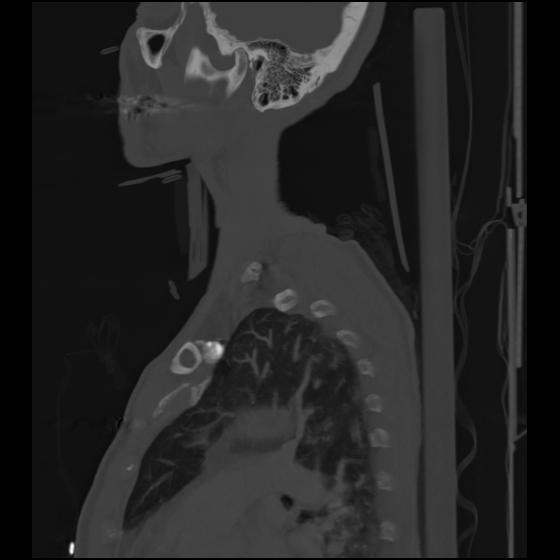

24 ANGIO,CE,Sag-MIP,5.000,ANGIO,Sag-MIP,